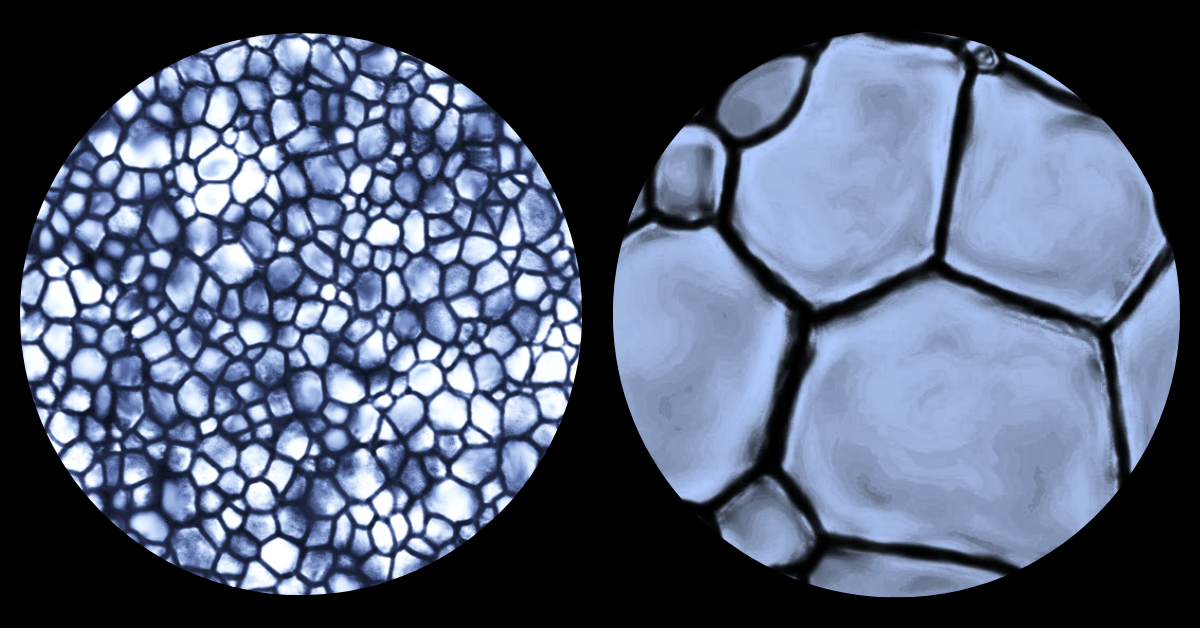

Ice crystals as seen through a microscope; small ice crystals on the left, and larger ice crystals on the right.

Ice growth, or the process of ice recrystallization, is an inevitable side-effect of freezing something. Over time, and with temperature fluctuations, ice crystals become larger and larger and cause a lot of disruption in cell membranes, which in turn damages or kills the cells.

“Small ice crystals are innocuous,” he says. “They’re like grains of sand on a Caribbean beach. They’re so small that they mould to your body and you can lay comfortably on the beach for an entire day. Now, let’s say those grains of sand were replaced by gravel or pebbles. That’s a lot less comfortable. Our cryopreservation technology prevents ice crystals from growing too large for comfort.”